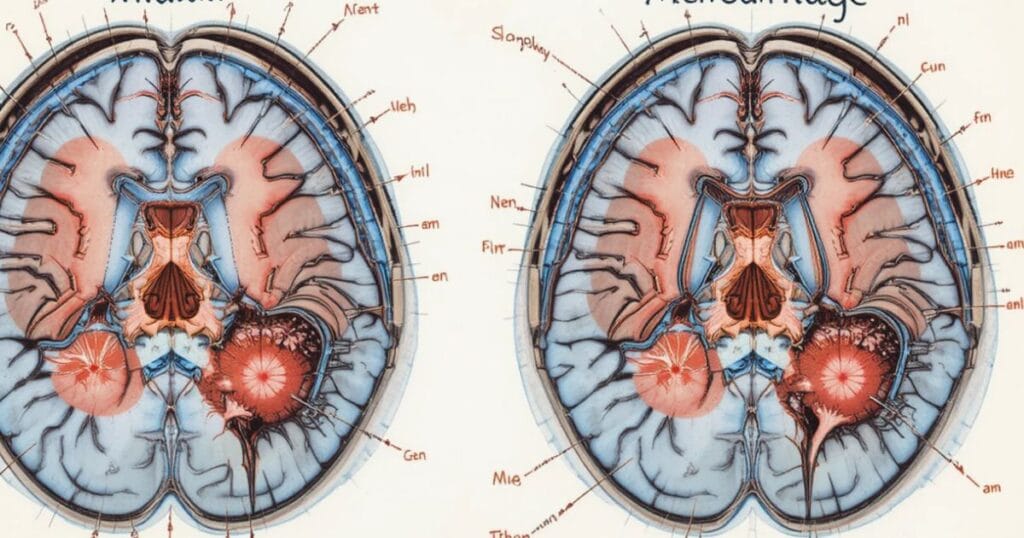

| Hematoma | Blood clot forming inside or around the brain. | Severe |

| Skull Fracture | Broken skull bone leading to open brain injury. | Severe |

Each of these injuries may require advanced brain scans after car accident such as CT or MRI to detect hidden damage.

A brain scan / CT / MRI helps detect brain hemorrhage car crash, contusions, or swelling. These advanced tools allow healthcare providers to create accurate treatment plans tailored to each patient.